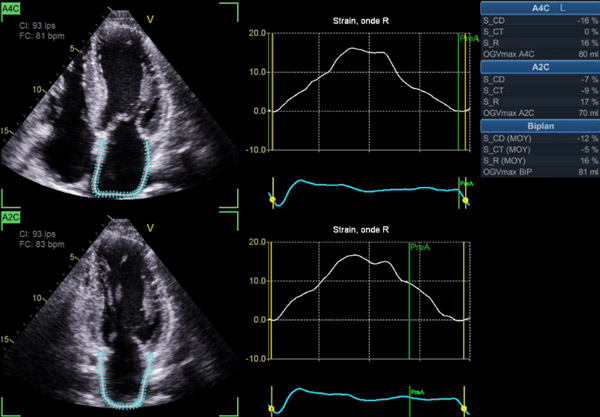

- Étude du strain atrial gauche, qui, < 13 % pendant la systole ventriculaire (phase réservoir), est aussi un facteur pronostique majeur, corrélé à la sévérité des symptômes, au risque thrombo-embolique, et à l’apparition d’arythmies atriales (Figure 4)4,5.

Figure 4 : Amylose TTR sauvage, 75 ans: en FA avec un DTI très altéré (s’ et e’ < 6 cm/s). Strain atrial < 20% mais non totalement effondré dans ce cas